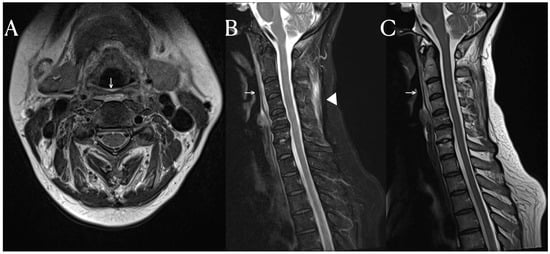

A C-spine MRI was performed, revealing evidence of degenerative spondylosis at the C5-6 level (Figure 1). The findings suggested potential causes for the patient’s pain, as considered by another hospital. However, the MRI also showed signal changes in the prevertebral area and the intermuscular fascia of the posterior neck area. While signal changes in such soft tissues are commonly observed in cases of traumatic injury, they are not frequently seen in cases of non-traumatic degeneration [3]. Inflammation in soft tissues is often observed in autoimmune diseases such as rheumatologic diseases and vasculitis [4]. SLE activates immune cells through nuclear self-antigens, inducing inflammation in connective tissues such as cartilage, ligaments, muscles, skin, blood vessels, and other soft tissues. The fascia is a tissue that encompasses these connective tissues, including interosseous membranes, tendons, entheses, epimysium, and vessels.

Figure 1.

Cervical spine MRI. In the T2-weighted sagittal image, mild edema and high signal changes in the prevertebral soft tissue (arrow) are found (A–C). Notably, on the fat suppression T2-weighted image, additional findings of high signal intensity in the posterior neck fascia (arrowhead) are observed (B).

The fat-suppressed T2-weighted image is a sensitive MRI sequence for confirming active enthesitis [5]. Furthermore, the intermuscular fascia, which contains a significant amount of fatty tissue, may not display abnormalities in T2-weighted images without fat suppression. In this patient, the T2-weighted images did not reveal any specific findings in the posterior cervical area, but significant signal changes were observed in the fat-suppressed T2-weighted view. Therefor, for diffential diagnosis, the fat suppression view provides valuable information. Similarly, this case demonstrates the importance of fat-suppressed T2-weighted images in identifying structural changes in fascia, which are frequently affected in systemic inflammatory diseases.